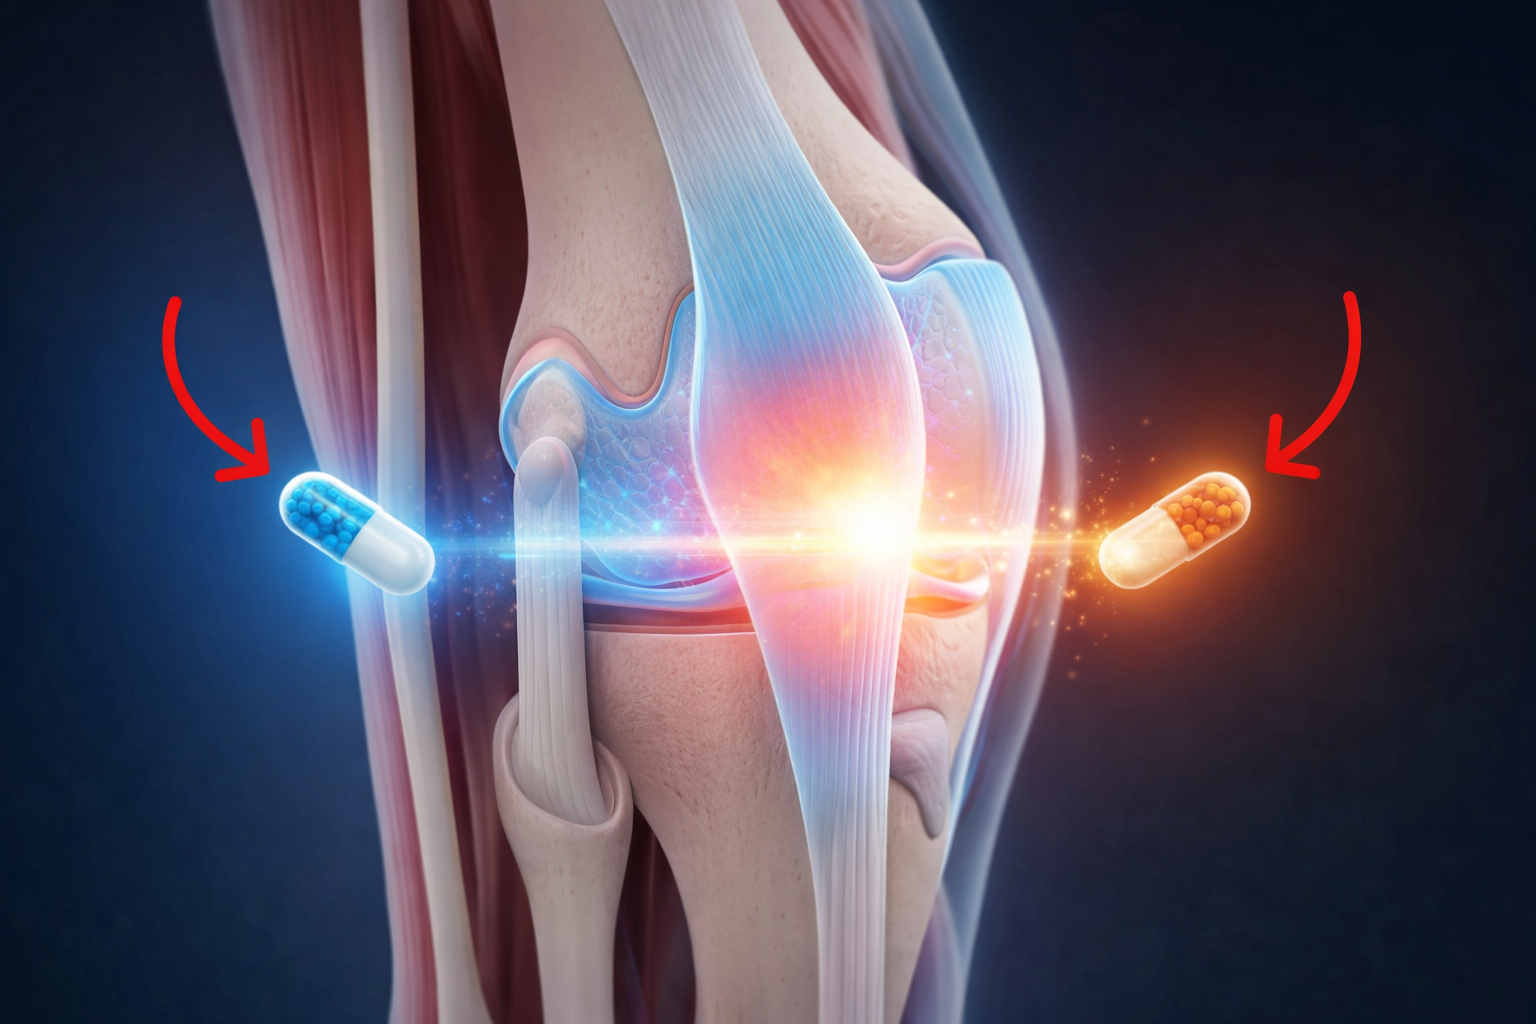

El dolor de rodillas es un problema que muchos ignoran hasta que se vuelve incapacitante. A menudo, comienza con señales sutiles que, si no se atienden, pueden llevar a una pérdida de movilidad. Pero, ¿sabías que hay nutrientes clave que podrían transformar tu bienestar articular? Aquí te contamos lo que necesitas saber para cuidar tus rodillas.

¿Por qué la Vitamina C es esencial?

La Vitamina C no solo refuerza tu sistema inmunológico; también es crucial para la producción de colágeno, el cual es vital para el cartílago. Sin suficiente vitamina C, el tejido cartilaginoso se debilita, afectando tus articulaciones. Pero, ¿cómo puedes asegurarte de obtenerla?